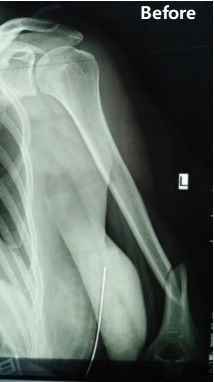

Case Sharing | Middle-to-distal third diaphyseal humerus fracture

Case Overview: A 48-year-old female patient was diagnosed as Fracture of the middle-to-distal third of the left humeral shaft (AO classification: type B1).